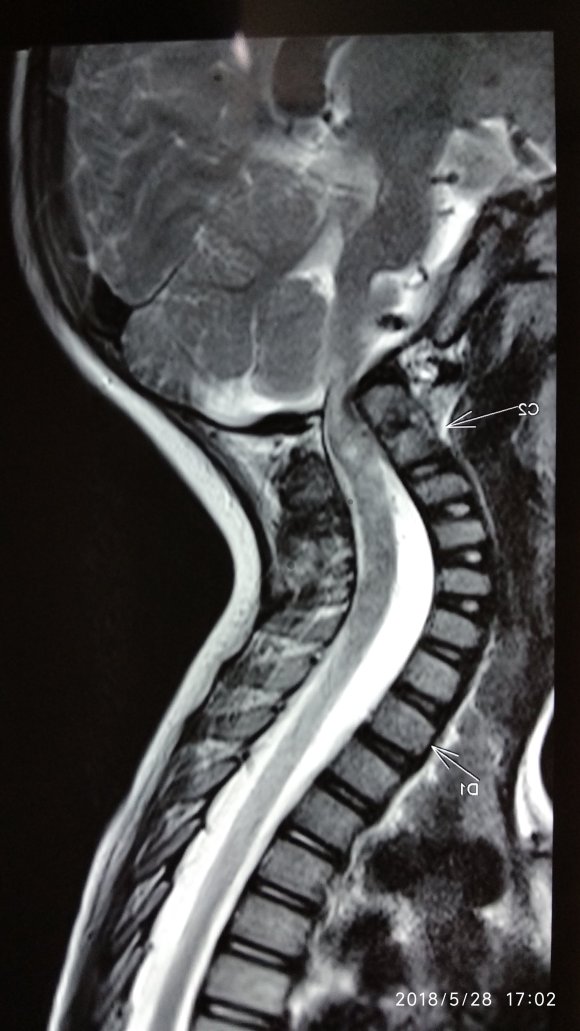

While many are simple spam or contracture of neck muscle some torticollis as shown in the picture below could harbour problems like compression of #spinalcord by #neck bones which have gone off alignment. These problems in the structure of neck bones occur at birth and are due to a developmental error in the shape of the neck vertebra.